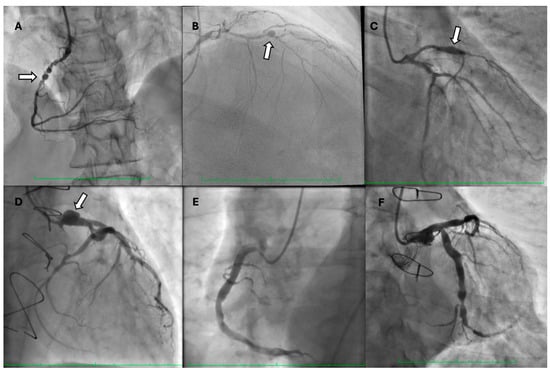

Invasive assessment of CAAE is based on coronary angiography (Figure 2). Nevertheless, this technique has limitations, as the actual size of the aneurysm may be underestimated in the presence of a thrombus. Furthermore, the turbulent flow in the dilated coronary segment can impair optimal imaging during coronary angiography []. Suboptimal imaging of the aneurysm hinders a thorough evaluation, including the presence of a thrombus. In such cases, intravascular ultrasound (IVUS) can be conclusive. Intracoronary imaging is a helpful tool for assessment of the accurate size of CAA, distinguishing between true aneurysms, pseudoaneurysms, and segments imitating aneurysms due to plaque rupture or adjacent stenosis, as it provides more precise visualization of vessel wall structures (Figure 3 and Figure 4). IVUS also allows proper stent sizing if percutaneous coronary intervention (PCI) is necessary.

Figure 2. Coronary angiograms showing (A) saccular aneurysm of the right coronary artery (arrow), (B) saccular aneurysm of the mid-segment of the left anterior descending artery (arrow), (C) fusiform aneurysm of the left anterior descending artery (arrow), (D) saccular aneurysm of the left main coronary artery (arrow), (E) coronary artery ectasia of the right coronary artery, and (F) coronary artery ectasia of the left circumflex artery.